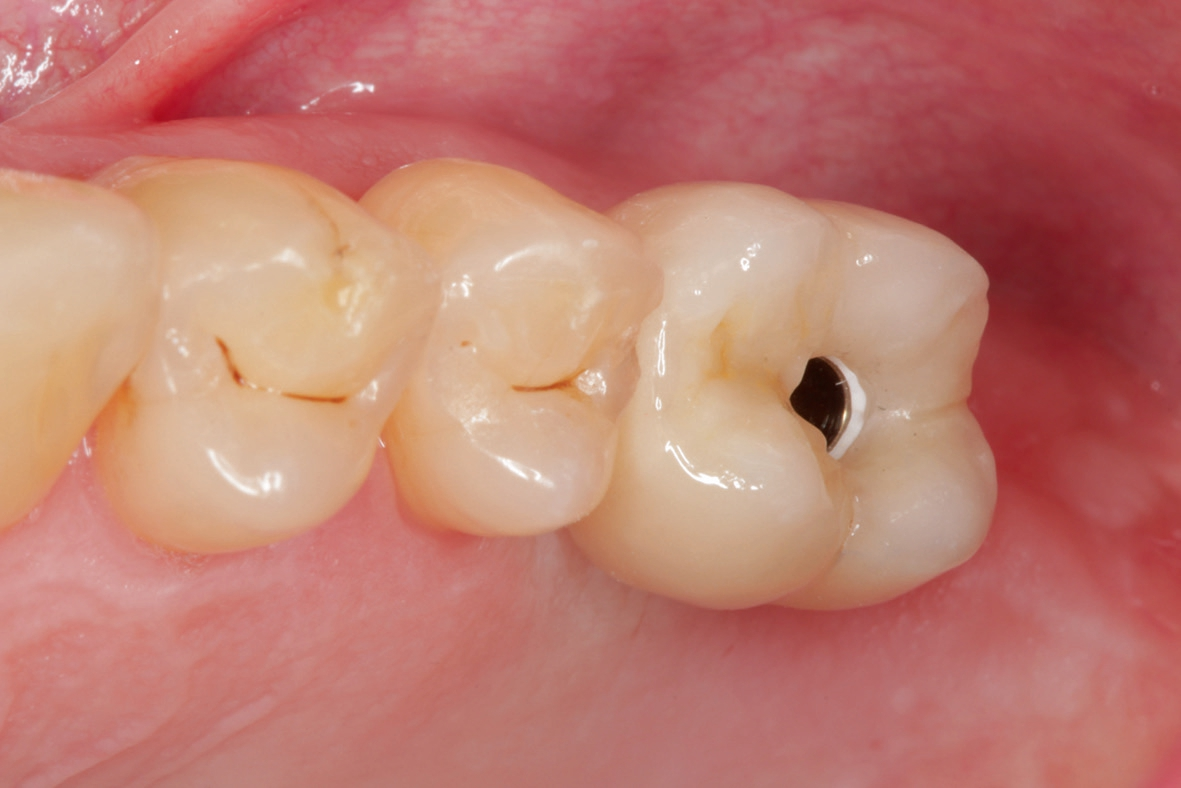

60-jähriger, männlicher Patient mit seit etwa acht Jahren bestehender Freiendsituation in regio 26/27. Drei Jahre zuvor wurde auf Position 36 ein PURE Monotype erfolgreich eingesetzt und prothetisch versorgt. Insgesamt ausgezeichnete Mundhygiene und absolut reizfreie Situation an 36. Der Wunsch des Patienten war nun die Versorgung der Position 26 mittels eines Keramikimplantates ohne größere chirurgische Intervention. Nach Anfertigung der dreidimensionalen Aufnahme (DVT) stellten sich ein ausreichendes transversales Knochenangebot und eine vertikale Höhe von ca. 5 – 6 mm zur Kieferhöhle dar, so dass ein interner Sinuslift und die Verwendung eines zweiteiligen Implantates geplant wurden. Das geringe vertikale Knochenangebot und die reduzierte Qualität verglichen mit dem Unterkiefer hätten bei Verwendung eines einteiligen Implantates mit transgingivaler Heilung ein Risiko für die erfolgreiche Osseointegration dargestellt. Zur Vorbereitung wurde die leichte basale Schleimhautschwellung beim Hals-Nasen-Ohren Arzt abgeklärt und der Patient führte täglich Nasenspülungen durch.

Die Übertragung der Implantatposition ins zahntechnische Laboratorium wird mittels offener Abformung mit individuellem Löffel und einem stabilen Polyäthermaterial vorgenommen. Die achsgerechte Position des Implantates ermöglichte die Anfertigung einer transocclusal verschraubten, verblendeten Zirkonoxidkrone auf einer Klebebasis. Die Besonderheit der Konstruktion ist dabei, dass das Metall der Klebebasis bei der fertigen Konstruktion komplett von Zirkon umschlossen ist. Dies erfordert eine hohe technische Präzision und eine spezielle „Verklebehilfe“ im Labor. Zur ersten Einprobe der Krone beim Patienten befestigen wir die Krone zunächst nur provisorisch auf der Klebebasis. Dies stellt sicher, dass sie bei eventuell notwendigen Korrekturen leicht gelöst und erneut gebrannt werden kann. Ist die Krone in Farbe und Form fertig gestellt, so muss sichergestellt sein, dass die endgültige Verklebung exakt in der gleichen Position auf der Klebebasis erfolgt, wie die zuvor einprobierte. Dafür fertigen wir einen Kunststoffschlüssel.

Vor Eingliederung der Krone wird die Hygienefähigkeit geprüft und sichergestellt, dass zukünftig in Okklusion und Artikulation keine traumatischen Kräfte auf die Restauration wirken. Nach Anziehen des erforderlichen Drehmoments wird der Schraubenkanal mit Teflonband gefüllt und ein okklusaler Verschluss mit Komposit vorgenommen.